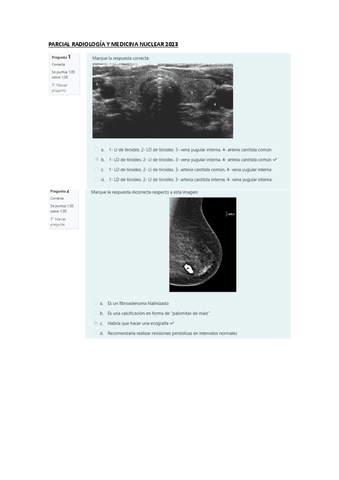

Exámenes - PARCIAL-RADIOLOGIA-Y-MEDICINA-NUCLEAR-2023.pdf